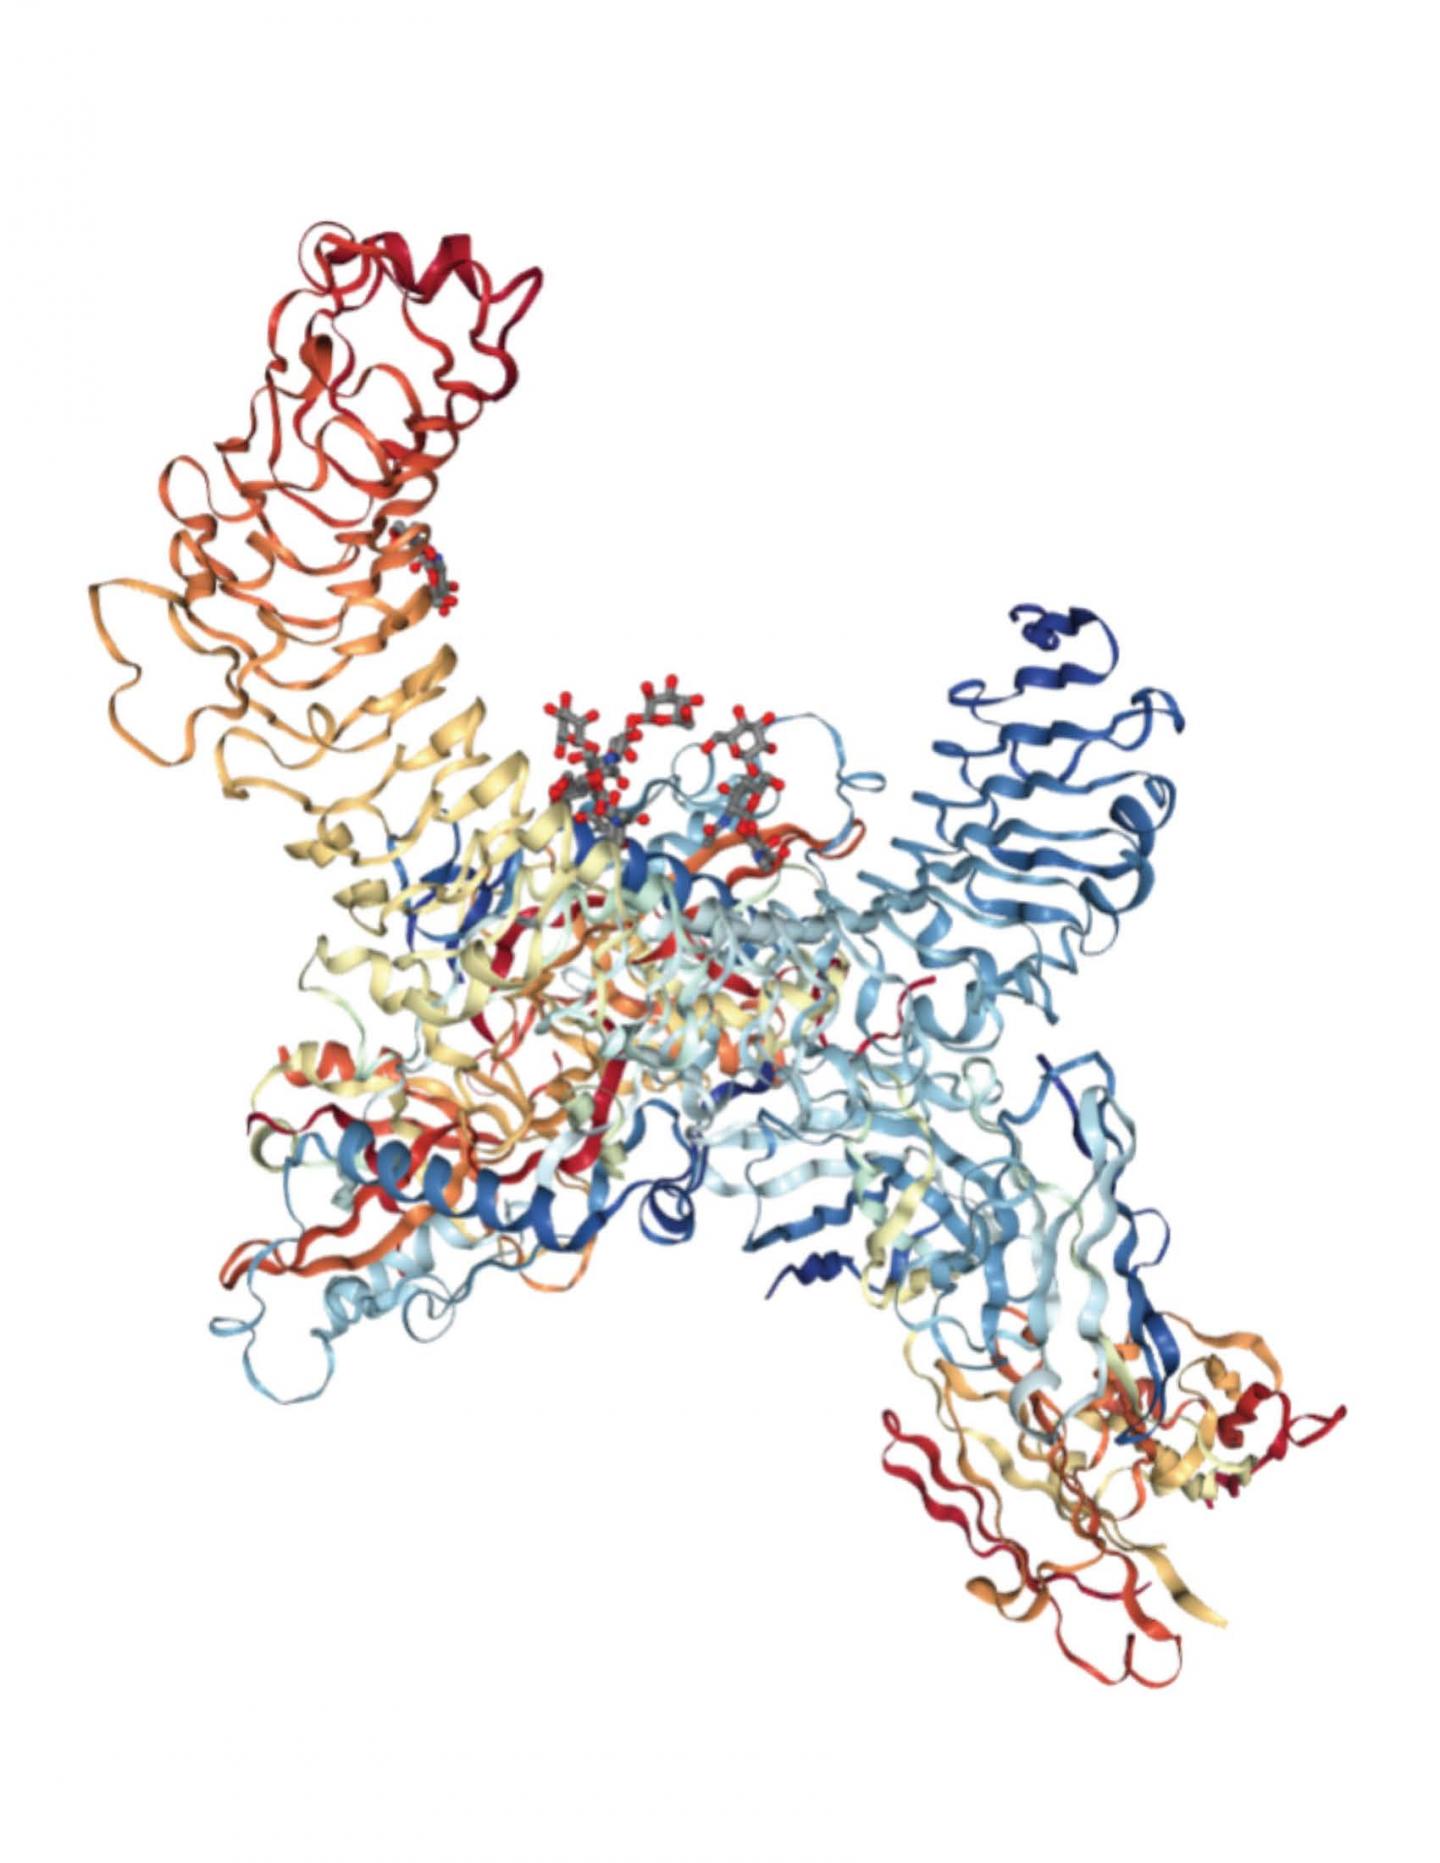

Immagine, struttura di GARP (LRRC32) in complesso con TGF-beta1 latente e Fab MHG-8. Credito: http://www.rcsb.org/.

Un altro attore importante coinvolto nella regolazione delle cellule Treg è TGF-beta che viene rilasciato dalle cellule e può regolare diverse parti del sistema immunitario. È noto che GARP è coinvolto nell’attivazione TGF-beta. Il lavoro di Li indica che GARP e TGF-beta lavorano insieme per regolare la migrazione di Treg verso l’intestino.